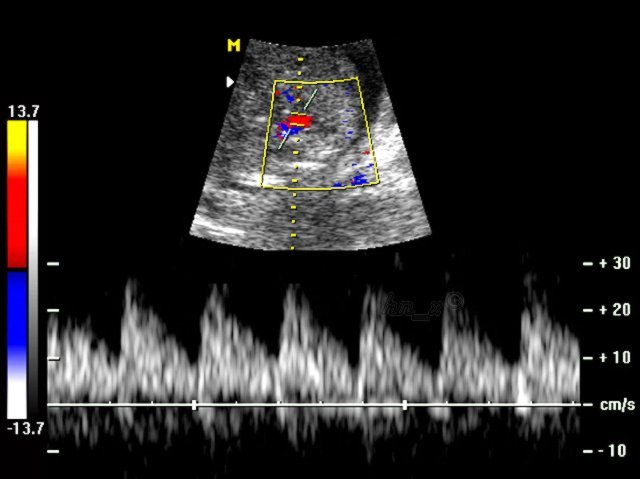

脐动脉血流频谱

图片尺寸1080x810